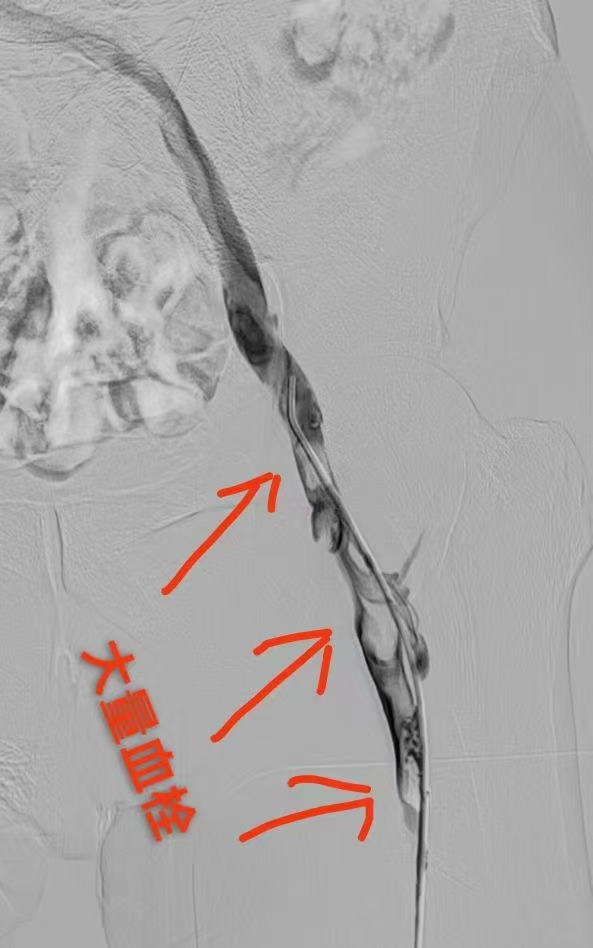

圖一為下肢血栓形成影像圖片 圖二為與圖一同部位經(jīng)過(guò)治療后血栓消失照片(圖片來(lái)源網(wǎng)絡(luò),如有侵權(quán)聯(lián)系刪除)